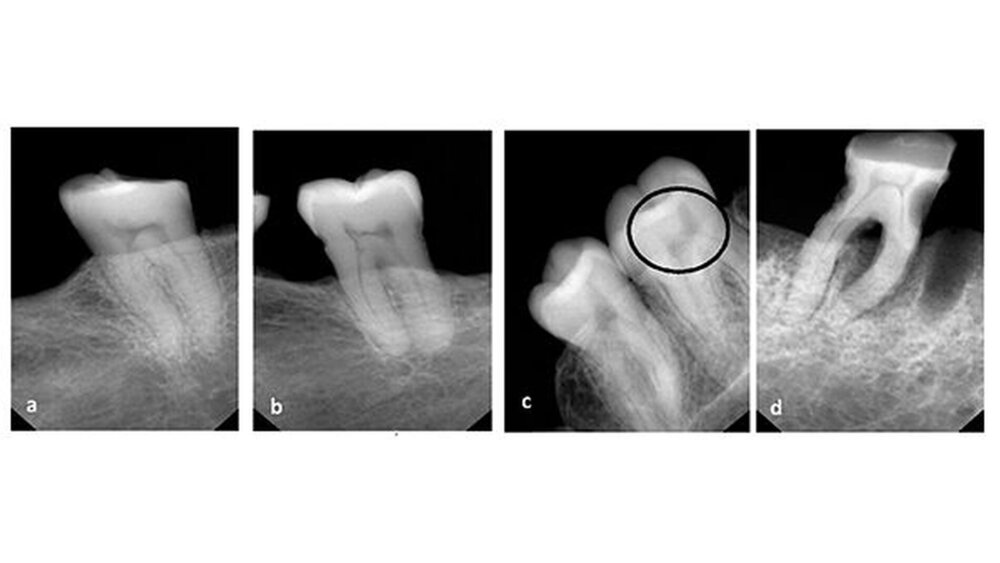

Die Form der Pulpa im gesunden Zahn ähnelt bekanntlich einem Bogen, der von zwei Katzenohren gekrönt wird, während sie bei Personen mit schwerem Vitamin D-Mangel asymmetrisch und verengt ist und typischerweise wie ein Stuhl mit harter Lehne aussieht.

Den Autoren zufolge gehen Vitamin-D-, Calcium- oder Phosphat-Mängel mit Veränderungen der Pulpenkammern aufgrund der abnormalen Mineralisierungen einher. Zellstoffanomalien könnten daher die erste Evidenzstufe für einen zuvor nicht diagnostizierten Vitamin D-Mangel sein.